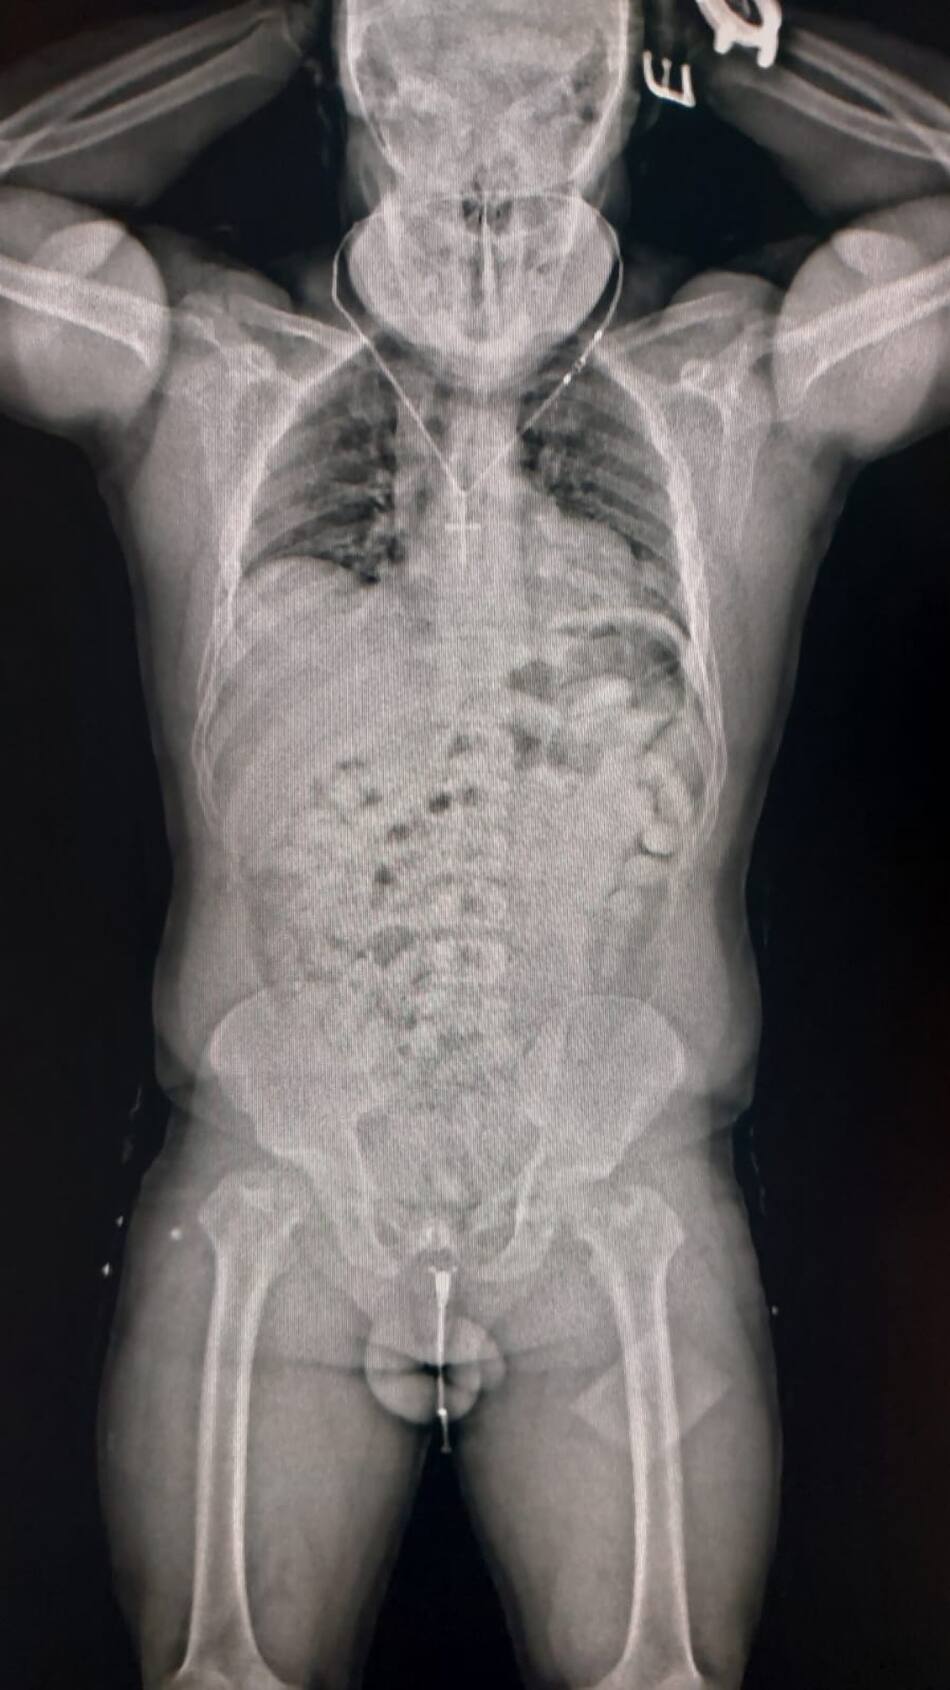

Aduana detuvo a un hombre que viaja a Europa con 84 cápsulas de cocaína en su organismo. Foto: Aduana.

Ante todos los indicios, los guardas inspeccionaron su equipaje, pero no encontraron nada. Dado que las dudas persistían, decidieron utilizar otro método de control: el body scan. Las imágenes confirmaron las sospechas del personal aduanero dado que mostraban cuerpos extraños.

Ante la posibilidad de que se tratase de un método de ocultamiento de estupefacientes, se internó al pasajero en un centro médico y lograron confirmar que había ingerido cápsulas con droga. En total eran 84 y contenían 1134 gramos de cocaína que en el país de destino se podría vender a USD 51 mil.